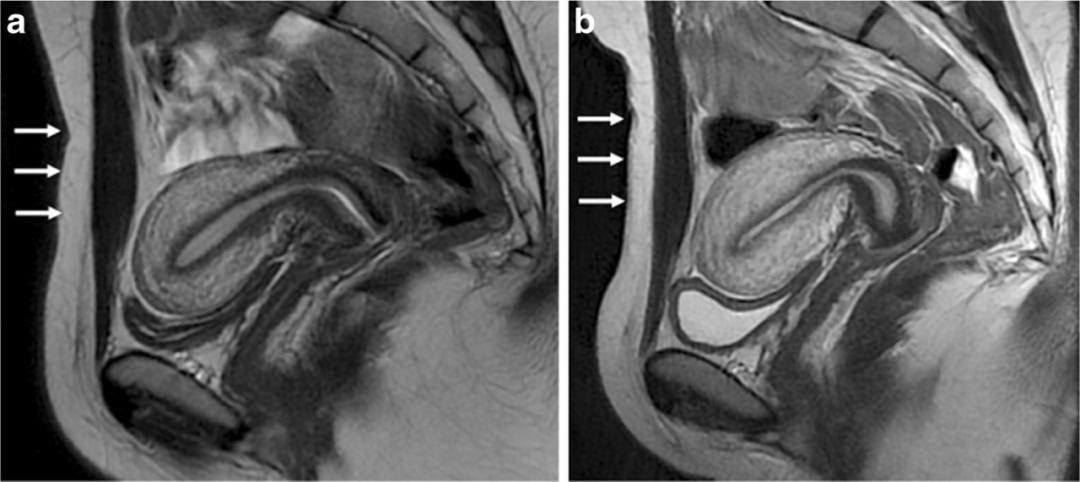

(a)在膀胱充盈且无肠道准备的情况下进行的成像图像质量欠佳,并且疾病可能被忽略。

(b)进行肠道准备后,注意中的高质量图像和直肠-乙状结肠前部的子宫内膜异位病变。